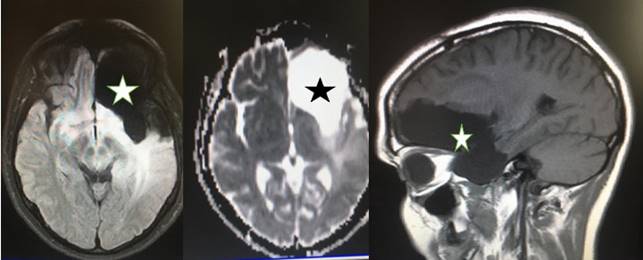

Figura 8: Glioma de bajo grado fronto-témporo insular izquierdo. Resonancia Magnética donde se observa la lesión trilobular.

Figura 9: A la izquierda, en la primera cirugía se identificó la fisura silviana (4), lóbulo temporal (3) y área del lenguaje (5). A la derecha se observa el abordaje transopercular temporal (flecha voluminosa), transopercular frontal (7), preservándose cerrada la fisura silviana (flecha pequeña). Los tags marcados muestran zonas de disfunción del lenguaje presentes al estímulo.